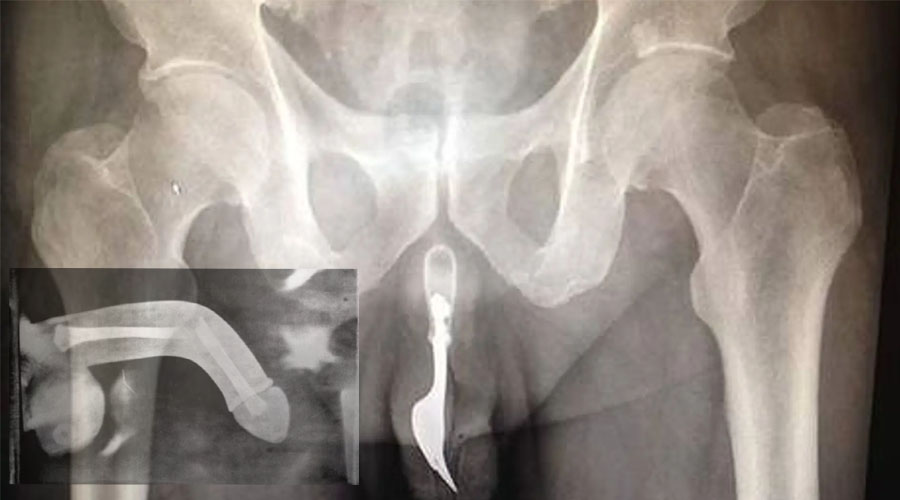

آلت تناسلی مردان فاقد غضروف و استخوان است و بافت نعوظی آن از سه سیلندر در کنار همدیگر می باشد که دو سیلندر آن حاوی بافت اسفنجی پرخون و یک سیلندر آن حاوی مجرای ادراری است. اطراف این سیلندرها بافت محکم و ضخیمی بنام تونیکا آلبوژینا قرار دارد. داخل سیلندرها می تواند خون زیادی هنگام تحریک جنسی وارد شود و در نتیجه آن طول و قطر آلت چند برابر شود. در نهایت با اینکه این ارگان تحمل فشار زیاد را دارد اما شکستگی آلت به اصطلاح پارگی همین قسمت است.

شکستگی آلت تناسلی یک وضعیت اورژانسی در اورولوژی محسوب میشود. این آسیب میتواند منجر به خونریزی وسیع، تورم، درد شدید و از بین رفتن سریع نعوظ شود. اگر بهموقع درمان نشود، احتمال بروز عوارضی مانند اختلال نعوظ، انحنای دائمی آلت و حتی آسیب به مجرای ادرار وجود دارد. به گفته دکتر کیوان آقامحمدپور این عارضه از اورژانسهای مهم اورولوژی است و اصطلاح شکستگی آلت تناسلی مردان با توجه به عدم وجود استخوان واژه مناسبی نمیباشد؛ در واقع منظور پارگی لایهی تونیکا آلبوژینه است که نقش کلیدی در حفظ نعوظ دارد.

تشخیص شکستگی آلت مردان در قدم اول بر اساس شرح حال بیمار و معاینه بالینی انجام میشود. صدای ترکیدن، درد ناگهانی، کبودی سریع و تغییر شکل آلت شواهد مهمی هستند. پزشک با مشاهده این علائم و لمس آلت میتواند احتمال شکستگی را بالا بداند. در مواردی که تشخیص دشوار باشد، از سونوگرافی داپلر یا MRI برای بررسی محل و شدت پارگی استفاده میشود. در صورت شک به آسیب مجرای ادرار، ممکن است اوروگرافی معکوس نیز درخواست شود.